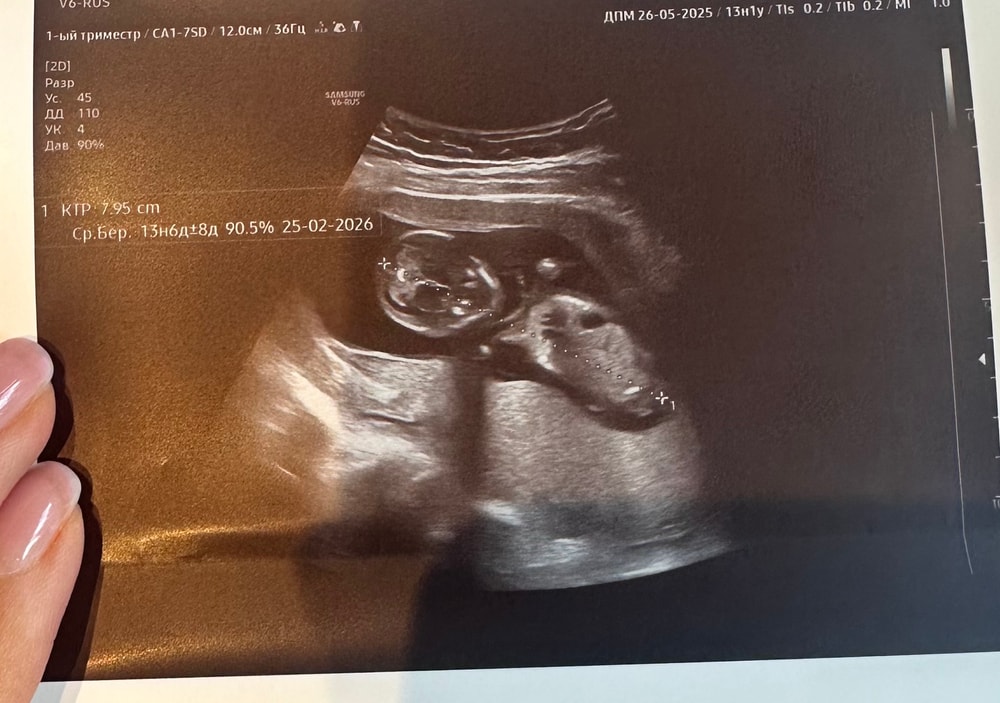

Ктр 13 недель

Анализы, скринингиДевочки, неделю назад делала скрининг ктр был 63 мм, спустя неделю сегодня пошла на узи чтобы убедиться что все ок.

врач сначала измерила в одном положении -65 мм, я говорю маловато - на прошлой был 63 мм. Она говорит а мы сейчас еще по-другому измерим и там уже 79 мм.

Фото в комментарии приложила